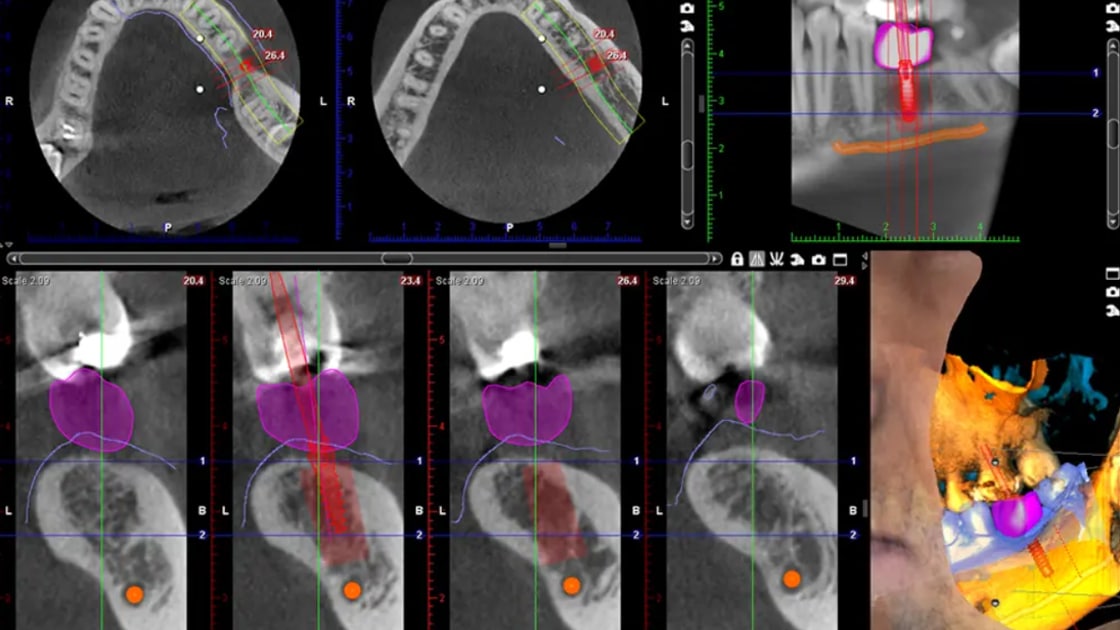

Our digital imaging and computer-aided design systems offer incredibly detailed views of your oral structures, enabling more precise diagnoses and treatment planning. This level of accuracy translates to better-fitting restorations and more successful outcomes.